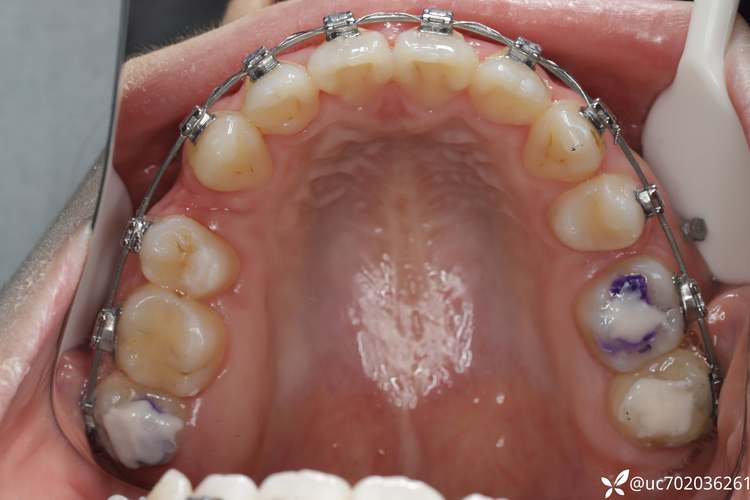

错位牙在口腔正畸中表现为牙齿偏离牙弓正常位置或排列异常,根据形态特征可分为以下几类,具体如下表:

| 类型 | 特征描述 | 临床表现 |

|---|---|---|

| 扭转牙 | 牙齿围绕长轴发生旋转,如上颌侧切牙“拧”着生长,或前磨牙旋转90°以上。 | 牙齿唇舌/颊舌侧厚度不均,刷牙时清洁死角多,易堆积牙菌斑;相邻牙齿间出现“三角间隙”,食物嵌塞频繁。 |

| 唇/舌向错位牙 | 牙齿偏离牙弓正常弧线,向唇侧(俗称“龅牙”)或舌侧(俗称“地包天”的部分表现)过度突出。 | 唇侧错位牙可能影响美观,微笑时露齿过多;舌侧错位牙易与对颌牙形成咬合干扰,导致咀嚼疼痛。 |

| 高位/低位错位牙 | 牙齿萌出或移动后,高于或低于牙平面,如“深覆合”时上前牙过低,或“开合”时后牙低位。 | 高位牙可能咬伤对颌牙龈,导致溃疡;低位牙与对颌牙无接触,咀嚼效率低,长期可能引发颞下颌关节紊乱。 |

| 近远中错位牙 | 牙齿在牙弓中前后位置异常,如尖牙(“虎牙”)向近中倾斜,占据侧切牙位置;或磨牙近中移动过多。 | 牙齿间邻接关系破坏,食物嵌塞;咬合时受力点偏移,易导致牙周组织创伤或牙齿松动。 |